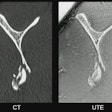

“Chronic low back pain and persistent hip pain after total hip replacement are often inadequately treated since conventional imaging techniques such as CT or MRI are unable to accurately identify the source of pain,” Mostert said.

A 47-year-old female patient with chronic pain in the left lower back/buttock with unknown cause. PET demonstrated focally increased FDG uptake at the left facet L3-4 l. MRI shows minimal fluid, but no edema. Follow-up PET-MRI after six months shows a similar pattern. The patient is on the waiting list for targeted facet joint infiltration (typically not covered by insurance in the Netherlands).Image courtesy of Marijn Mostert